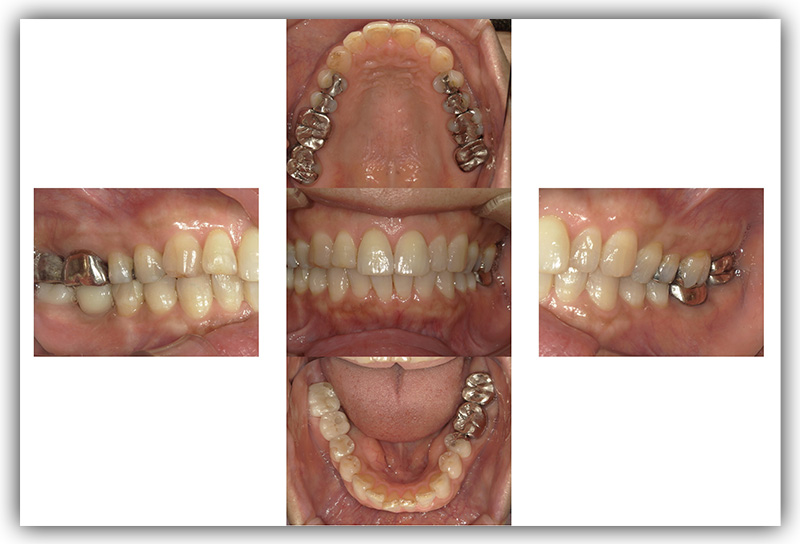

CASE_01

70代男性(インプラント)

- 患者さん情報(年齢・性別)

- 70代 男性

- 主訴

- 歯を失ってしまったところにインプラントに入れたい

- 治療箇所

- 7箇所

- 治療方法

- インプラント

- 費用

- 約320万円

- 治療期間

- 約1年